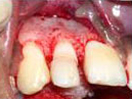

An Innovative Technique of saving a Tooth with Fracture Extending Sub-Gingivally (Chisel Type Fracture)

Showing picture line

Extending Palatally and

Sub-Gingivally.

X-ray showing

picture line

Labial Soft Tissue

Reflected

Palatal Soft Tissue